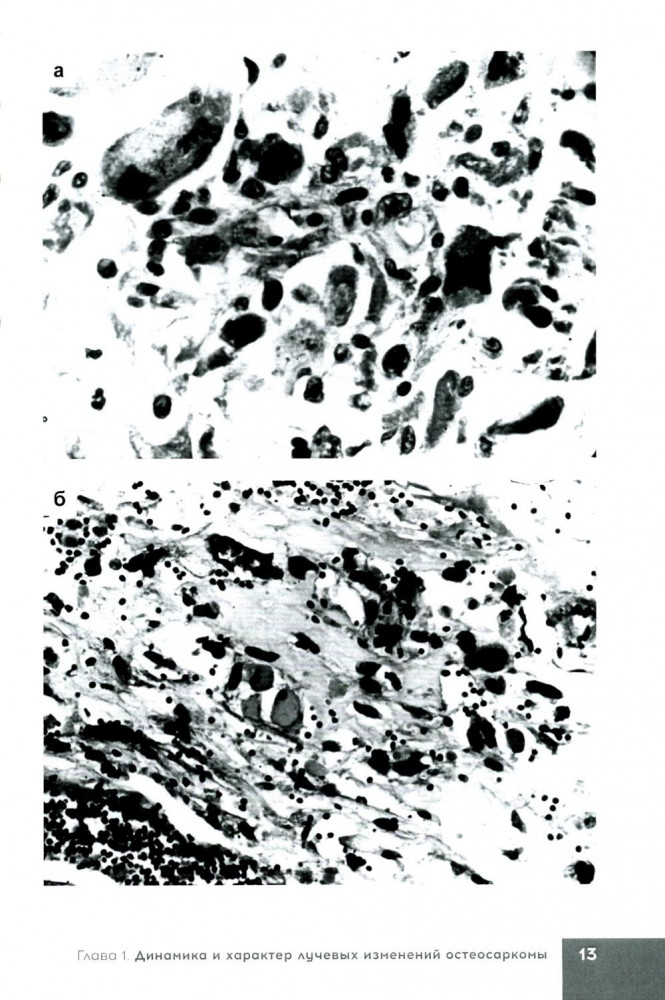

💳 Оплатить за товар можно при получении 🇰🇿 Есть бесплатная доставка по Казахстану от 1 дня 🎁 Копите бонусы с каждой покупки Серия: Библиотека цитолога В книге представлены возможности морфологических исследований (патолого-анатомических и цитологических) в определении морфофункционального состояния клеток и тканей двух типов первичных злокачественных новообразований костей до проведения, в динамике и после завершения курса лучевой терапии. Показана значимость использования полученных данных в выборе метода лечения, в т. ч. и лучевого, в оценке прогноза и эффективности лучевой терапии при злокачественных новообразованиях костей. |